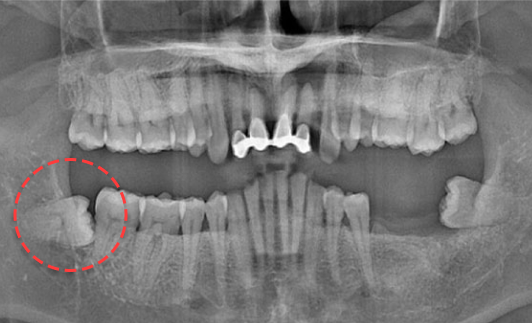

왼쪽 하악 매복 사랑니 발치 Before X-Ray

치료시작일

2020.05.24

AFTER

왼쪽 하악 매복 사랑니 발치 After X-Ray

치료종료일

2020.06.29

왼쪽 하악 매복 사랑니 발치